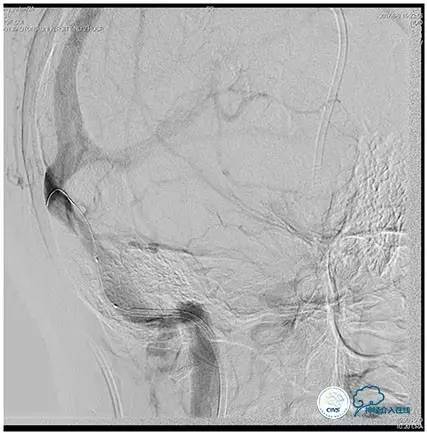

术后造影

术毕远近端压力差为:0

术后即刻患者头痛缓解。

停用脱水药,次日腰穿压力160mmH2O。